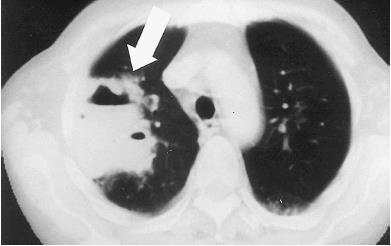

据报道,一男子曾因扫墓后出现咳嗽、胸痛、发热等症状,胸部CT表现为“树芽征”,最终确定为曲霉菌感染,患上肺炎。“树芽征”是反映小气道病变常见的征象,常见于肺结核,也可见于其他细菌、真菌(如曲霉菌)等感染。

例1:患者长期口服免疫抑制剂,近期发热,痰中带血

图1 胸部CT

图1 胸部CT诊断:IPA。

空气新月征是曲霉菌的典型CT。当然,只说一个空气新月征,那也太枯燥了,不能满足大家的胃口。